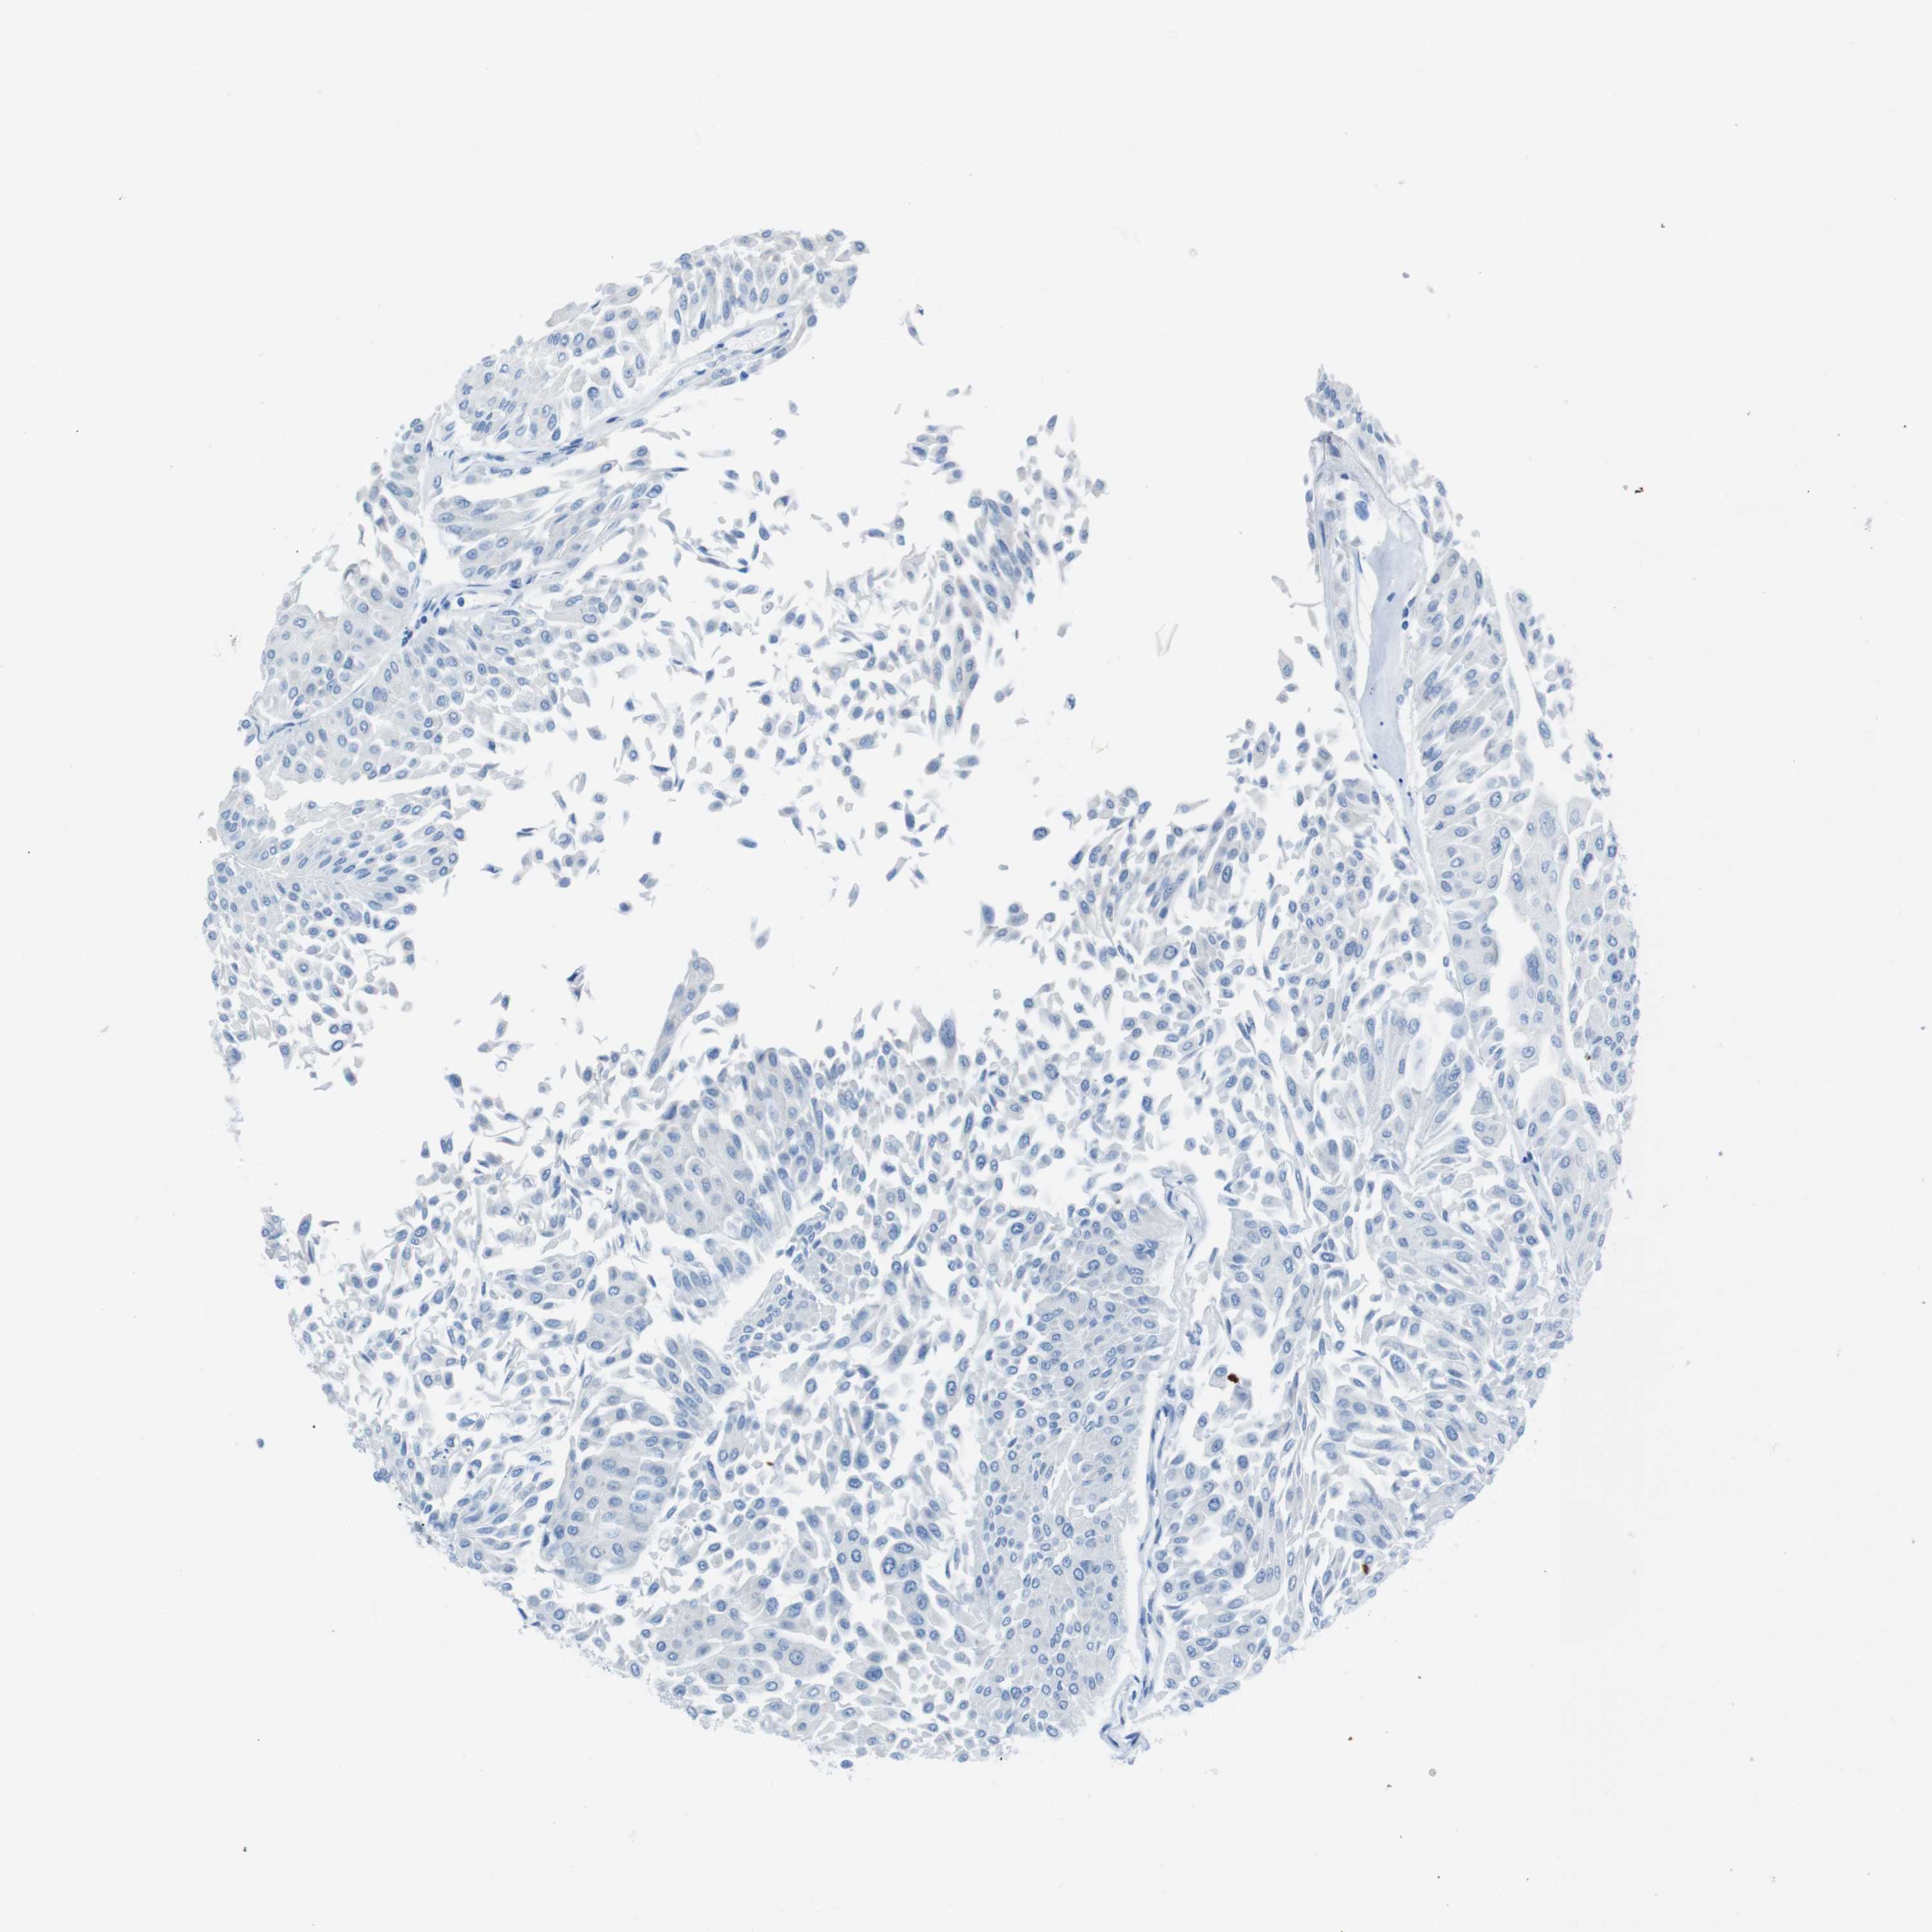

UROTHELIAL CANCER - Protein expressioni

A mouse-over function shows sample information and annotation data. Click on an image to view it in a full screen mode. Samples can be filtered based on level of antibody staining by selecting one or several of the following categories: high, medium, low and not detected. The assay and annotation is described here.

Note that samples used for immunohistochemistry by the Human Protein Atlas do not correspond to samples in the TCGA dataset.

Antibody stainingi

Antibody staining in the annotated cell types in the current human tissue is reported as not detected, low, medium, or high, based on conventional immunohistochemistry profiling in selected tissues. This score is based on the combination of the staining intensity and fraction of stained cells.

Each image is clickable and will lead to virtual microscopy that enables deeper exploration of all samples and also displays staining intensity scores, fraction scores and subcellular localization as well as patient and tissue information for each sample.

Antibody HPA013392

Antibody HPA015600

Antibody CAB004417

Staining

High

Medium

Low

Not detected

Intensity

Strong

Moderate

Weak

Negative

Quantity

>75%

75%-25%

<25%

None

Location

Nuclear

Cytoplasmic/membranous

Cytoplasmic/membranous,nuclear

Urothelial carcinoma, Low grade

Urothelial carcinoma, High grade